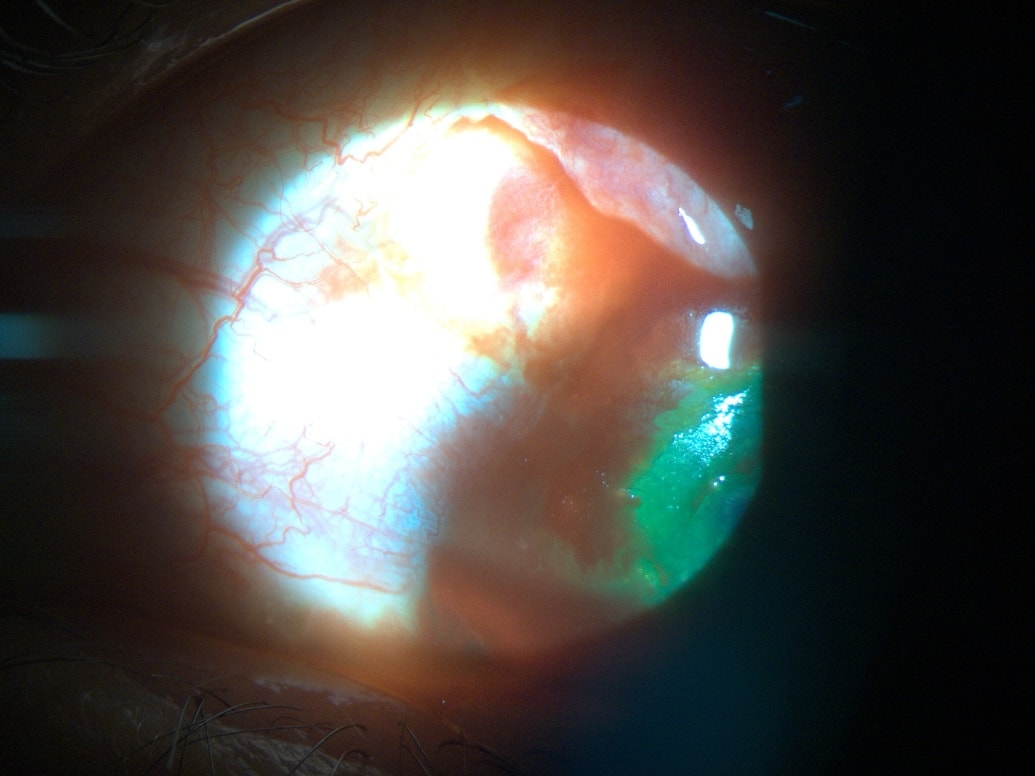

Een ander geval dat tijdig spoedeisende hulp kreeg, was dat van patiënt Nguyen VL (geboren in 1992, woonachtig in de gemeente Tan Ha, district Lam Ha). Tijdens het oogsten van koffie werd de patiënt hard in zijn rechteroog geraakt door een tak die terugkaatste, wat hevige pijn en bloedingen veroorzaakte. Familieleden brachten de patiënt onmiddellijk naar het Saigon Da Lat Oogziekenhuis voor spoedeisende hulp.

Bij onderzoek stelde de arts vast dat de patiënt hoornvliesbeschadigingen en uitgebreide scheurtjes in het bindvlies had, waarvoor een operatie nodig was om het bindvlies te herstellen en medicatie om bloedingen te stoppen en infecties te voorkomen.